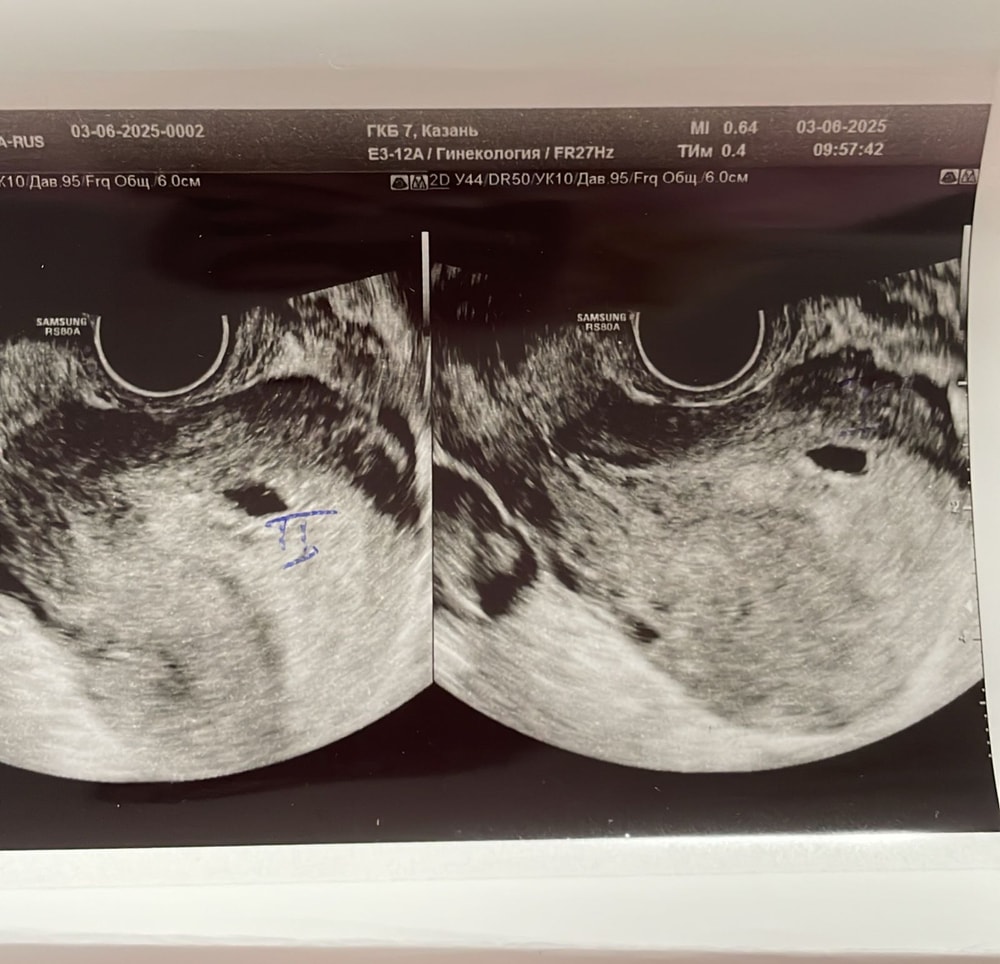

Выглядит, как большая гематома. Пожалуйста, обратитесь к гинекологу. У меня так было. Исход был плачевным. Желаю вам удачи. И больше здравомысляя, чем было у меня 🙏

Kristina, похоже на то😂 вчера девочки писали что это гематома,а сегодня в больнице,сказали что второе пя,но срок маленьки эмбриончиклв еще не видно

Евгения, я так понимаю что думают что 2 ПЯ.

Но мне кажется 1 ПЯ в под ним гематома

Ксеня, выглядит как отслойка, я уже выше написала почему. Пусть ошибаюсь и это второе пя 🙏

Лариса , как только датчик засунула,врач сразу сказала,а вы знаете что у вас 2 пя,я говорю нет. Потом стала сомневаться,я спросила а это может быть гематома,она сказала,что 100% не гематома,так как внутри нет жидкости,то есть крови. Я говорю,а почему один очерченный,а другой нет. Она сказал,что возможно один может просто отставать в развитии. И назначила контрольное узи через неделю

Евгения, в двух местах была на узи сегодня,нигде не сказали про гематому

Вот узи с перво клиники